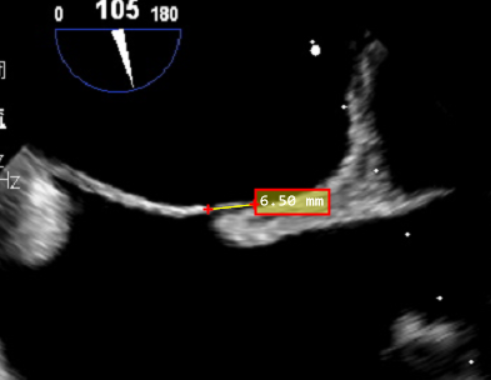

经食道超声:房间隔卵圆窝处见卵圆贴合欠佳,可见一隧道样缝隙,大小约1.3~1.8mm,CDFI可在该处探及低速过隔彩流。

PFO间隙2mm,隧道长度8.2mm(主动脉短轴);

隧道长度14mm(双房切面);

2、PFO参数:隧道裂隙宽约2mm;卵圆孔隧道长度8.2mm(主动脉短轴)14.6mm(双房切面)。